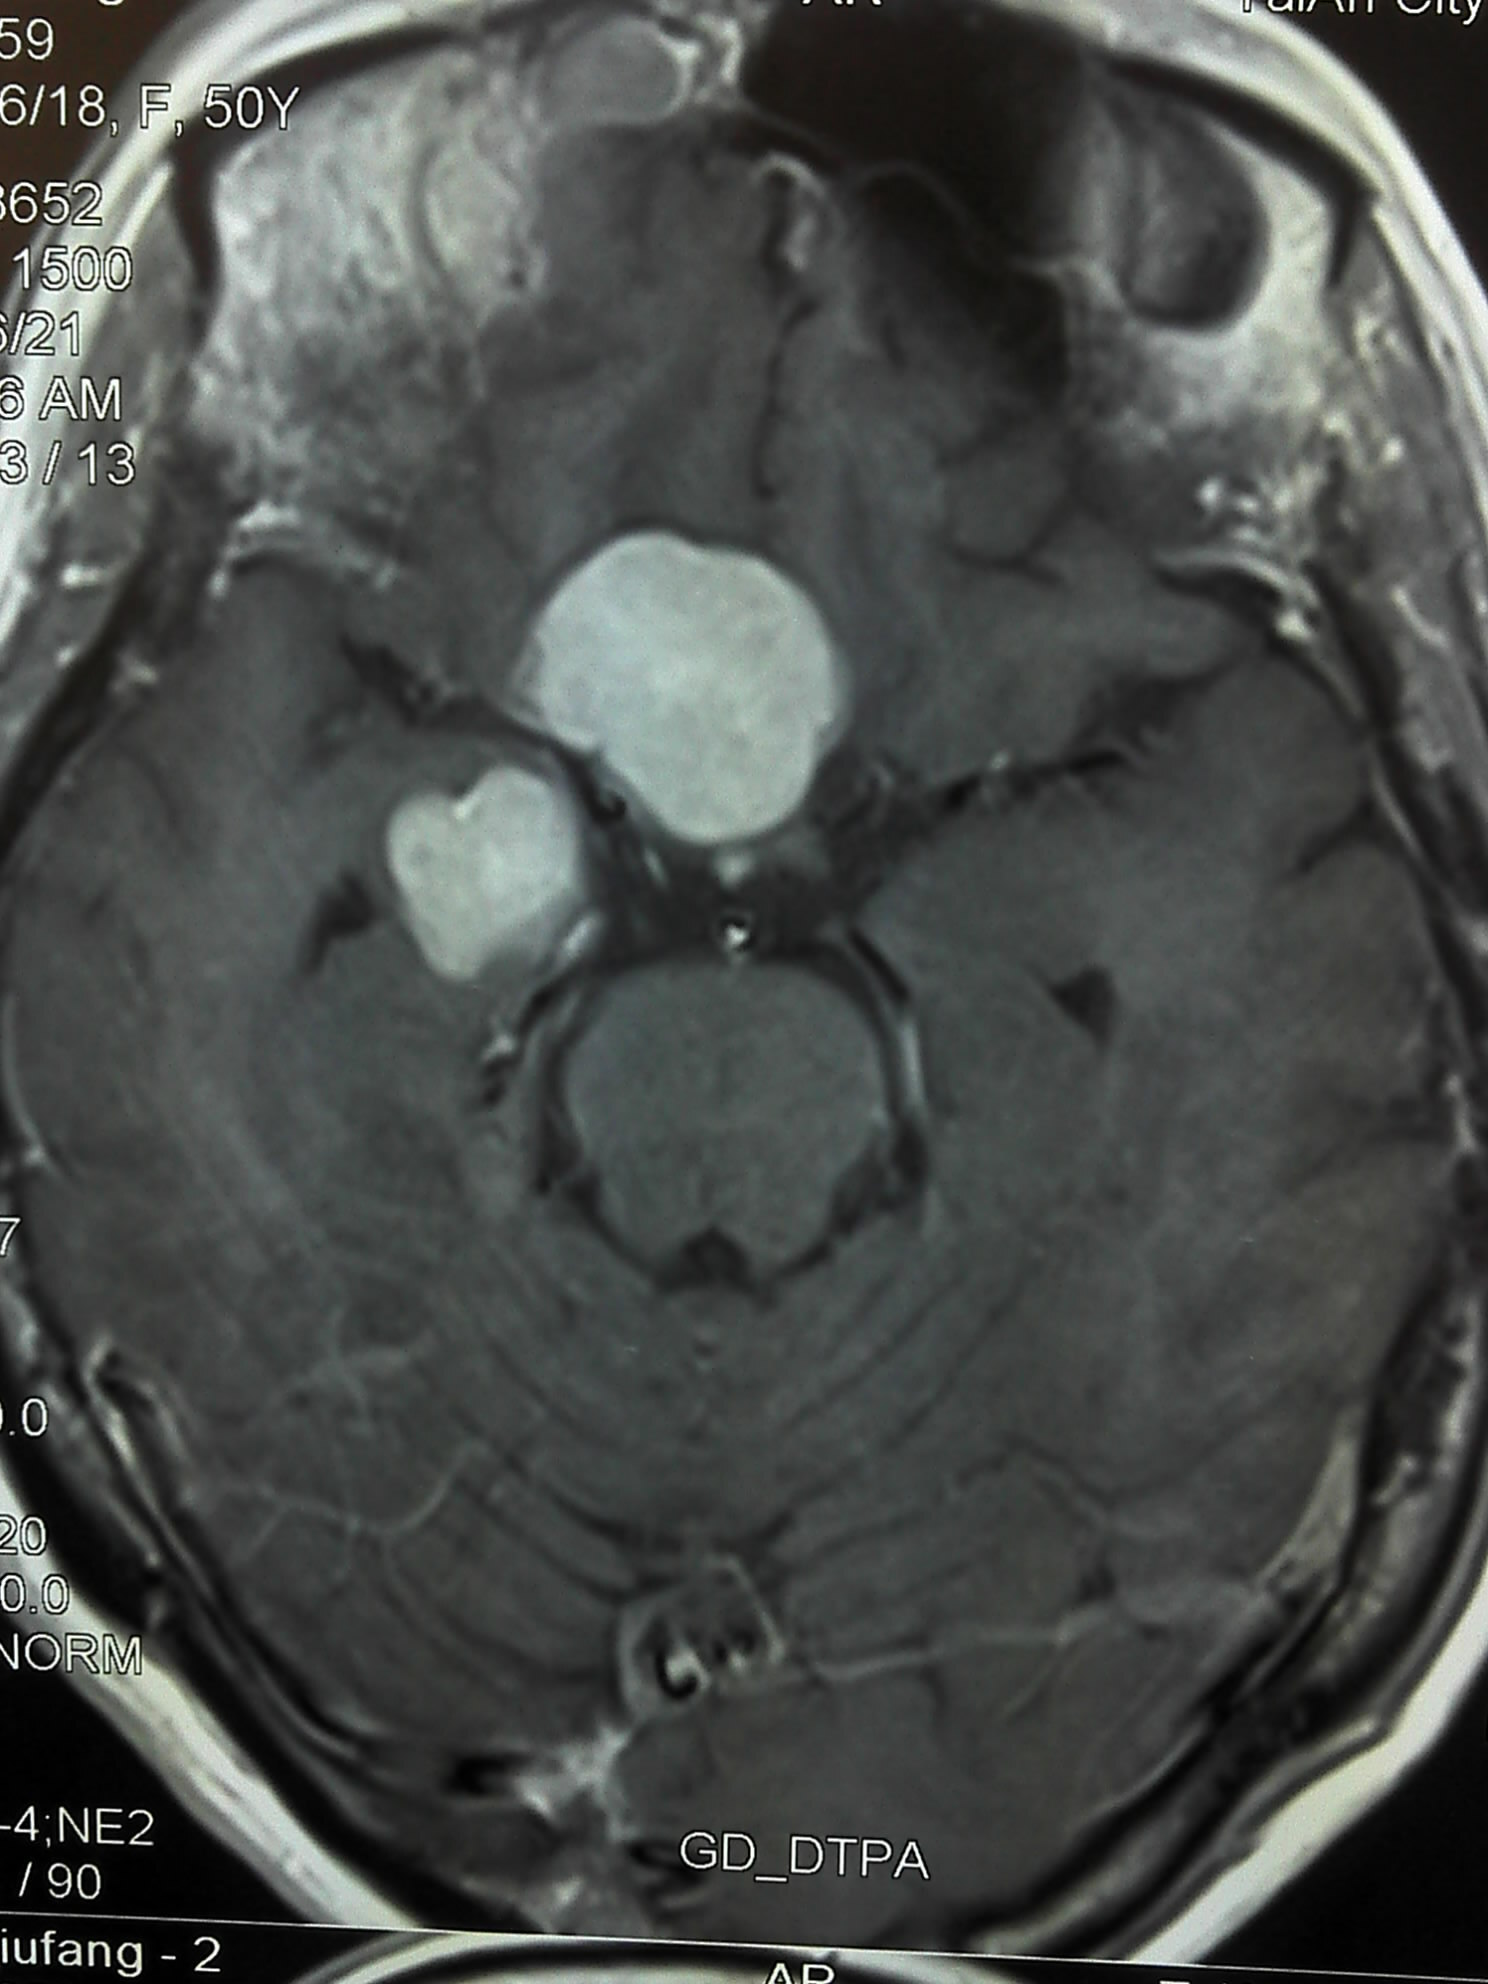

下图是放疗结束后复查的脑核磁: